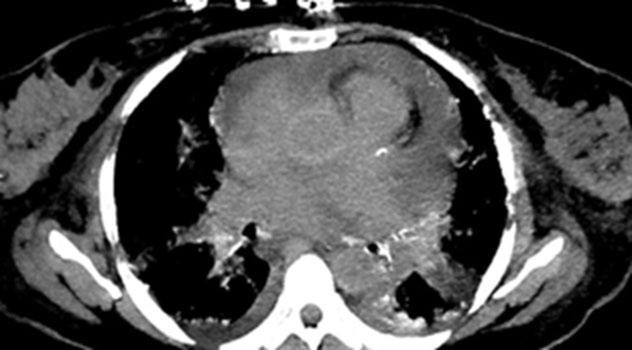

Receive our free newsletters and alerts Get the latest updates on all our upcoming journals and receive first-class insights into ground-breaking news and advancements in medicine across multiple therapeutic areas. www.emjreviews.com Join our mailing list

Turn static files into dynamic content formats.

Create a flipbook